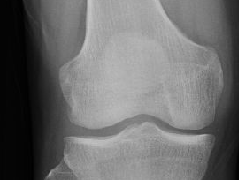

• 关节积脂血症(lipohemarthrosis)

关节积脂血症(lipohemarthrosis)